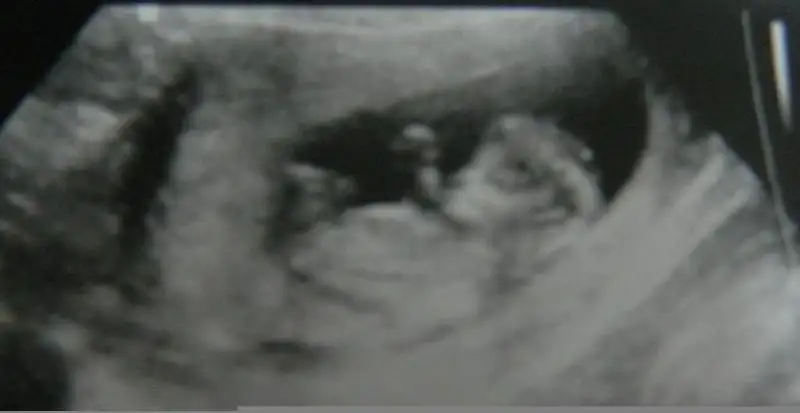

lütfen yorum yazın çok merak ediyorum 12 haftalık görüntüsü,